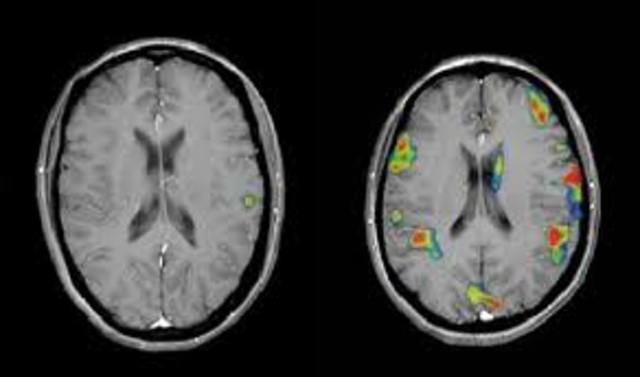

• Resonancia  Magnetica Funcional

Resonancia Magnetica Funcional

mide los cambios metabólicos que ocurren dentro del cerebro. Puede utilizarse para examinar la anatomía el cerebro, determinar que parte del cerebro está manejando funciones críticas, evaluar los efectos del derrame o enfermedad cerebral, o guiar el tratamiento cerebral. La RMN puede detectar anormalidades dentro de cerebro que no se pueden encontrar con otras técnicas por imágenes.